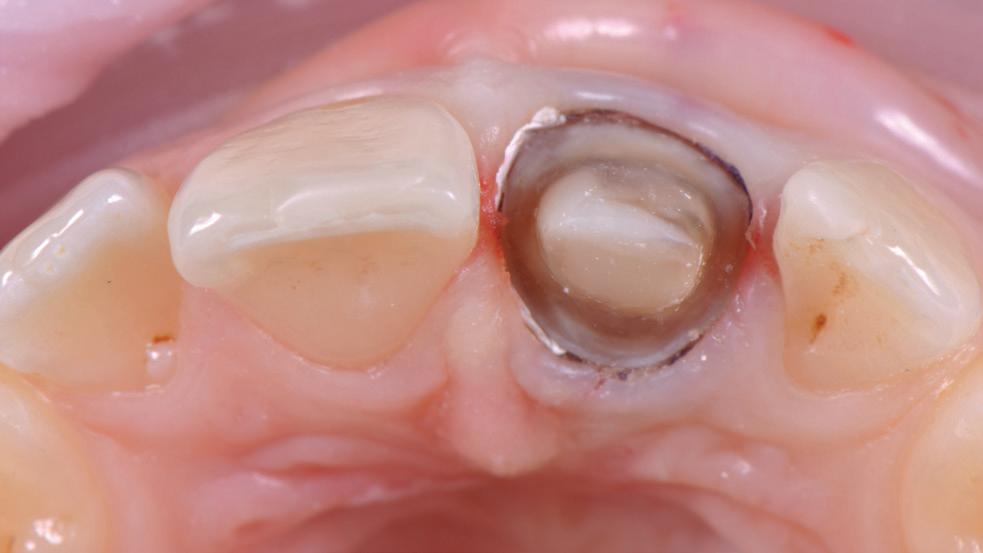

Adopting sharp safe methods is essential in all dental practices. The Ultra Safety Plus and Ultra Safety Plus Twist provides the dental team with the necessary tool to provide safe practice. If sharp safe habits are not expected of each team member, the risk of a sharp injury increases.